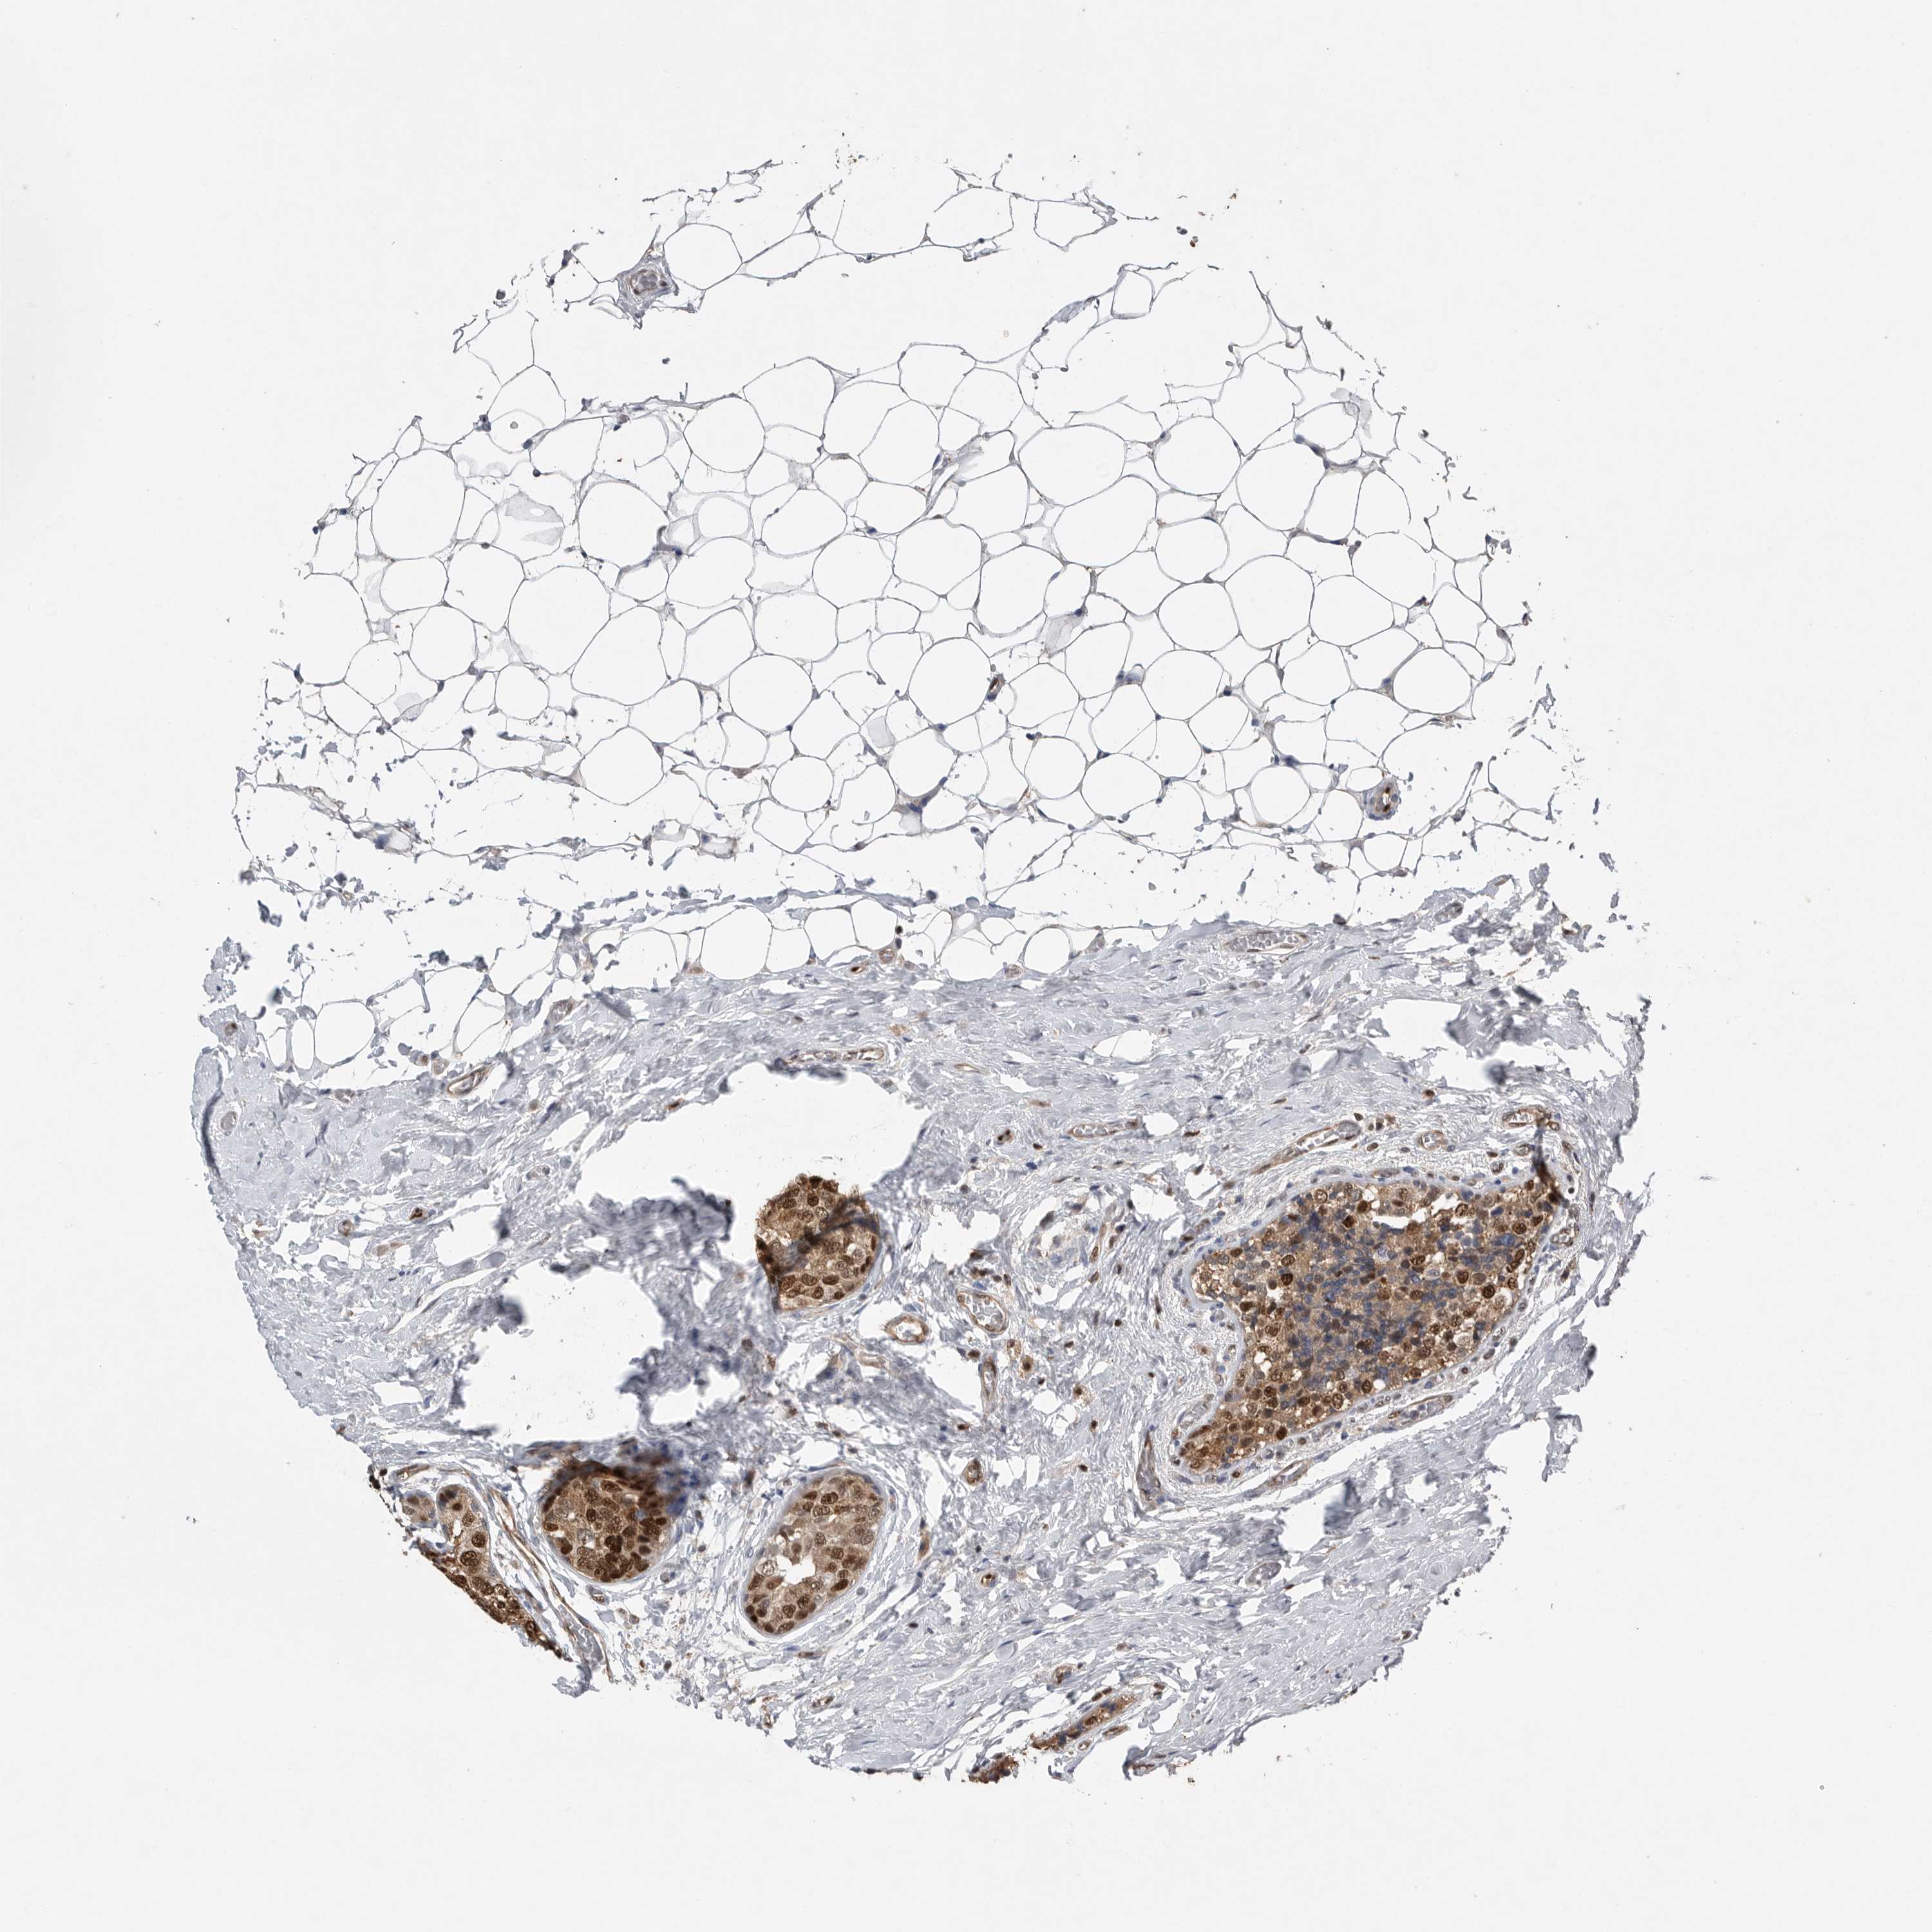

CANCER BREAST CANCER Show tissue menu

BRCA TCGA BRCA VALIDATION PROTEIN EXPRESSION

ANTIBODIES

AND

VALIDATION